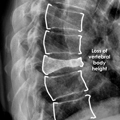

• שבר דחיסת חוליות אוסטאופורוזיס

אוסטאופורוזיס עלול לגרום לקריסת חוליות כתוצאה מלחץ קל. קיפופלסטיקה בלון משחזרת את הגובה, מייצבת את העצם ומקלה על הכאב.

בלון kyphoplasty הוא הליך זעיר פולשני שנועד לתקן שברי דחיסה בחוליות על ידי צמצום וייצוב השבר. הוא מטפל בשברים פתולוגיים של גוף החוליה עקב אוסטאופורוזיס, סרטן או נגעים שפירים.